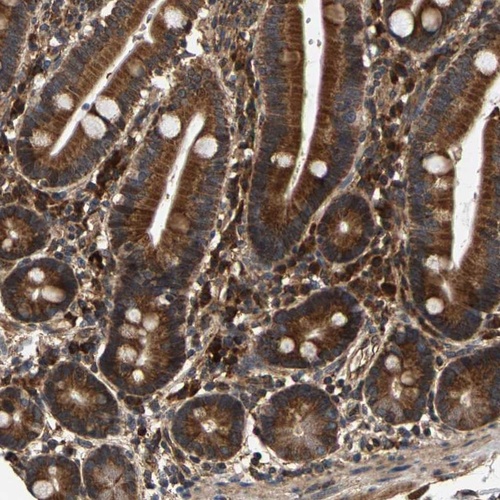

Immunohistochemical staining of human duodenum shows strong cytoplasmic positivity in glandular cells.